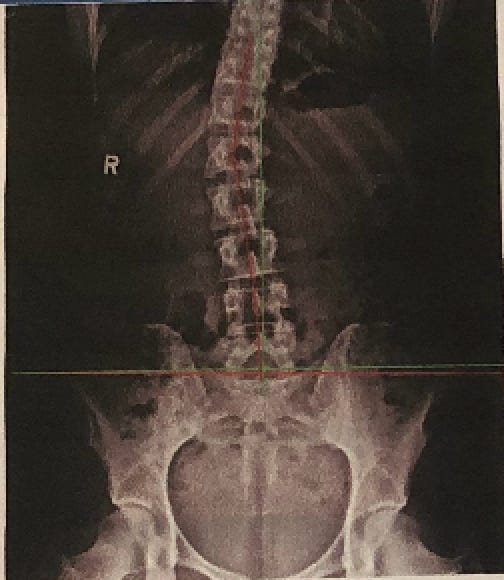

Without staying on top of my genetic imbalances, compensation can happen and happen quickly. Sometimes it’s a tight left hamstring, other times it’s been a tight left piriformis or a tight left calf. Lately it’s been a combination of all three, and it all stems from my scoliosis.

I was diagnosed with idiopathic scoliosis when I was 15 and the highest my curve ever measured was 23°—not terrible considering the degree of curvature that some of my family members have (thanks, Dutch genes! I got the scoliosis without the height.) It wasn’t enough to have me put in a brace nor be a candidate for surgery, and so I was sent to PT to complete endless clam shells.